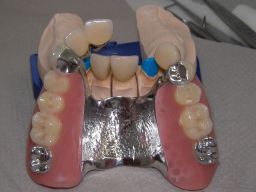

Die Unterseite, die später der Mundschleimhaut aufliegt, ist im Bereich der Druckknöpfe hochglanzpoliert und damit gut pflegbar, was wichtig für gesundes Zahnfleisch an diesen Stellen ist. Das Kugelattachment (Druckknopf) ist das Preci-Clix (Fa. Ceka). |

Die Zähne auf der Prothese sind aus verarbeitungstechnischen Gründen auch heute meist noch aus Kunststoff, auch wenn teurere Keramikzähne möglich wären. Kunststoff verschleißt über die Jahre, der Biß verändert sich. Um letzteres zu verhindern, sind hier zusätzlich Metallkauflächen eingearbeitet, die sich nicht verändern werden. Auch Verbindungselemente verschleißen. Um den Verschleiß reparieren zu können, sollte der Verschleiß aus dem Mund in die Prothese gelenkt werden. Im Mund deshalb hier 4 harte Titankugeln, die passenden Druckknöpfe in der Prothese aus Kunststoff, wo sie leicht ausgewechselt werden können. | |